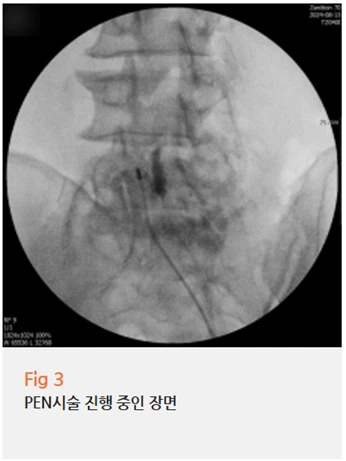

저는 환자분께 당일 PEN 시술을 권해드렸습니다.

PEN은 Percutaneous Epidural Neuroplasty의 약자로,

가느다란 카테터를 경막외강 내로 삽입해서 유착을 박리하고,

눌린 신경 주변에 직접 약물을 투여하는 최소침습적 치료입니다.

쉽게 말하면, 단순히 염증만 줄이는 게 아니라

신경이 눌려 있는 부위를 직접 찾아가서

유착을 떼어내고 압박을 풀어주는 겁니다.

시술은 국소마취로 진행됐고,

시간도 그리 오래 걸리지 않았습니다.